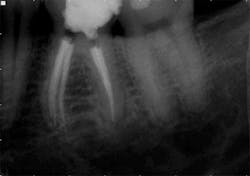

Treatment: Following an inferior alveolar block and intraosseous anesthesia, access was made and caries were removed. After access, the main canals were irrigated with sodium hypochlorite and a glide path was established with hand files to working length. The dentin triangle was removed with Protaper S1 and the final instrumentation was completed using WaveOne. The two canals in the distal root joined to form a broad canal in the facial-lingual dimension and exit a common foramen. After shaping was completed in the mesial root, an isthmus of pulp tissue was identified under the microscope and a mid-mesial canal was identified following exploration of this area. However, the initial orifice was small and the canal path irregular, thereby preventing the establishment of a glide path to the apex. To open the orifice, a series of hand files was used just below the pulpal floor. It was then possible to pass a 10 file to the mid-root and the orifice opening was completed with a Vortex orifice opener size 20/08. The natural glide path was then instrumented to the apex with a 10 file and a Vortex Blue 15/04 was utilized to enhance the shape. A series of Vortex Blue instruments was used to create the final shape of 30/04. In this clinical scenario, Vortex Blue is the ideal rotary instrument system because of the cutting efficiency and combination of cyclic fatigue resistance and flexibility.

The WaveOne shape in the four main canals allowed for obturation with a warm vertical technique, because the heat source could be delivered to within a few millimeters of the apex. However, the constricted shape of the mid-mesial was not amenable to this technique and a GuttaCore carrier was placed to take advantage of the hydraulics and create a dense, three-dimensional seal.

This case illustrates an alternative method of hybridizing the shaping technique based on the natural canal anatomy. In spite of highly variable anatomy in the mesial root, different instrumentation and obturation techniques yielded a final outcome that cannot be distinguished radiographically.